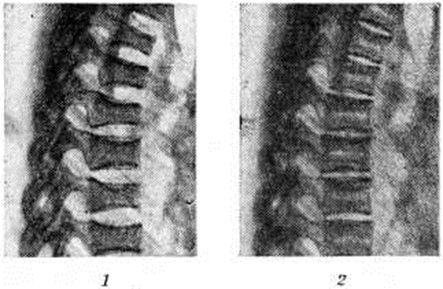

Артериальная гипертензия (смотри полный свод знаний Гипертензия артериальная) является ранним и постоянным симптомом Иценко – Кушинга болезнь Она отличается стойкостью, высокими цифрами систолического и диастолического артериальное давление и определяет развитие расстройства мозгового кровообращения, ретинопатии, первичносморщенной почки. Остеопороз — частый, но более поздний симптом Иценко – Кушинга болезнь; клинически он проявляется болями чаще в позвоночнике и ногах. Боли нередко достигают такой интенсивности, что ограничивают движения. У лиц, которые заболели в детском возрасте, наблюдается задержка роста, раннее лобковое оволосение при задержке полового развития, костный возраст у больных подростков отстаёт от паспортного. Тяжёлая форма остеопороза сопровождается переломами костей. У женщин нарушается менструальный цикл и детородная функция, у мужчин снижается либидо и развивается импотенция (смотри полный свод знаний). По мере прогрессирования заболевания нарушается деятельность почек; в анализах мочи часто обнаруживаются альбуминурия, гематурия, цилиндрурия; снижается концентрационная способность почек. Иногда появляются симптомы почечнокаменной болезни (смотри полный свод знаний). Нарушения углеводного обмена проявляются чаще всего пониженной толерантностью к углеводам. Содержание сахара в крови превышает нормальный уровень, у трети больных отмечается глюкозурия. При истощении инсулярного аппарата как осложнение может развиться сахарный диабет. Сочетание симптомов гиперкортицизма с проявлением выраженных симптомов сахарного диабета описано как синдром Ашара—Тьера (так называемый диабет бородатых женщин). Повышенный катаболизм белков выявляется отрицательным азотистым балансом. Характерны гипокалиемия, холестеринемия, но холестерин-лецитиновый коэффициент не изменяется. В периферической крови регистрируется эозинопения, лимфопения, нейтрофильный лейкоцитоз, иногда выраженный гиперхромный эритроцитоз. Значительно нарушена функция свёртывающей системы крови; коагулопатия протекает по типу тромбогеморрагического синдрома, требующего особой настороженности при оперативных вмешательствах. У больных снижена резистентность к различным инфекциям, часто возникают рецидивирующие заболевания кожи, мочевых путей, пневмонии. Неврологические синдромы отмечаются у подавляющего числа больных Иценко – Кушинга болезнь Амиотрофия (смотри полный свод знаний) развивается в проксимальных отделах конечностей, что вызывает истончение конечностей и снижение силы сокращения их мышц. Сопоставление данных клинико-электромиографического и морфологический исследований показало, что первичным является поражение мышечной ткани (смотри полный свод знаний Атрофия мышечная). В генезе болевого синдрома основную роль играет сдавление спинномозговых корешков, обусловленное остеопорозом позвонков с деформацией межпозвонковых отверстий и отёком самих корешков. Симптомы пирамидной недостаточности проявляются в виде сухожильной гиперрефлексии на одной стороне тела в сочетании с центральным парезом VII и XII пар черепных нервов на той же или другой стороне. Стволово-мозжечковый синдром проявляется нистагмом, двусторонней недостаточностью отводящих (VI пара) нервов, двусторонними патологический рефлексами, атаксией и дискоординацией движений; пирамидный и стволово-мозжечковый синдромы обусловлены сосудистыми нарушениями в головном мозге (мелкоочаговые размягчения или кровоизлияния) или изменениями гипертензионно-гидроцефального характера, развивающимися вследствие артериальной и внутричерепной гипертензии. На начальных этапах Иценко – Кушинга болезнь неврологический симптоматика ограничивается амиотрофическим и болевым синдромами; при прогрессировании заболевания с развитием артериальной и внутричерепной гипертензии неврологический симптоматика может дополняться пирамидным и стволово-мозжечковым синдромами, которые указывают на неблагоприятный прогноз. При Иценко – Кушинга болезнь нередко наблюдаются изменения со стороны психической сферы больных: развивается раздражительность, ухудшение памяти, снижение интереса к окружающему. Могут возникать ипохондрические состояния (смотри полный свод знаний Ипохондрический синдром), сенестопатии (смотри полный свод знаний), эпилептиформные припадки, психозы. Выраженность симптомов заболевания зависит от степени гиперкортицизма. Течение болезни обычно хроническое. Различают лёгкую, среднюю и тяжёлую формы заболевания. В отдельных случаях заболевание быстро прогрессирует. Тяжёлая форма характеризуется наличием осложнений. Осложнения. Наблюдаются самопроизвольные переломы костей, сахарный диабет и часто сопутствующий ему фурункулёз, нефросклероз. Возможны тяжёлые психические расстройства. Угрозу для жизни представляют кровоизлияния в мозг, сердечно-сосудистая недостаточность, сепсис как результат снижения сопротивляемости к гнойничковой инфекции. Диагноз ставится на основе клинической, рентгенологическое и лабораторных данных. Рентгенологическое исследование занимает ведущее положение в установлении диагноза Иценко – Кушинга болезнь. Для изучения состояния гипофиза проводится рентгенография, а в отдельных случаях и томография турецкого седла (смотри полный свод знаний Гипофиз). Аденома гипофиза, обусловливающая Иценко – Кушинга болезнь, как правило, имеет незначительные размеры и на рентгенограммах турецкого седла не выявляется, поэтому следует учитывать наличие значительного остеопороза стенок турецкого седла при небольшой выраженности деминерализации костей свода черепа. Увеличение размера турецкого седла наблюдается редко. Из многочисленных рентгенологическое методик исследования надпочечников основными являются пневморетроперитонеум (смотри полный свод знаний), инфузионная урография (смотри полный свод знаний) и ангиография (смотри полный свод знаний), которые имеют самостоятельное и взаимодополняющее диагностическое значение. Надпочечники на рентгенограммах и томограммах увеличены в размерах, имеют не чёткие, неровные контуры, негомогенную ячеистую или зернистую структуру (так называемый липопаренхиматозные надпочечники). рентгенологическое изменения подлежат дифференциальной диагностике с кортикостеромой (смотри полный свод знаний), при которой соседние органы могут смещаться и деформироваться, а форма поражённого надпочечника искажается и приобретает вначале более выпуклое, а впоследствии шаровидное очертание с интенсивностью тени и гомогенной структурой. Эффективным методом выявления изменений в надпочечниках является ангиография (артериография и флебография). Наиболее информативна селективная артериография (смотри полный свод знаний), однако из-за значительной вариабельности строения артериальной системы надпочечников в отдельных случаях возможны диагностические ошибки. В связи с меньшей вариабельностью венозной системы надпочечников более перспективна флебография (смотри полный свод знаний). При Иценко – Кушинга болезнь отмечается увеличение диаметра сосудов надпочечников, их деформация, изменение типичной ангиоархитектоники за счёт увеличения размеров и числа анастомозирующих ветвей, удаётся выявить и контуры органа, при ангиографии необходима дифференциальная диагностика с кортикостеромой. Остеопороз имеет обычно однородный мелкозернистый характер, отличаясь этим от крупнопятнистых деструктивных очагов при воспалительных или бластоматозных процессах. Наблюдается остеопороз чаще в средних, нижних грудных и верхних поясничных позвонках, реже в верхних грудных и ещё реже в шейных позвонках. Тела позвонков уплощаются, деформируются по типу «рыбьих» (рис. 2, 1). Остеопороз рёбер и грудины проявляется небольшой интенсивностью теней костей и груботрабекулярной их структурой; места переломов бывают окружены быстро возникающими избыточными мозолями. Столь же часто остеопорозу подвергаются кости таза, кистей и стоп. Рост и дифференцировка скелета у детей отстают в среднем на 3 года. Процесс восстановления структуры костей является одним из основных критериев эффективности лечения Иценко – Кушинга болезнь; у детей наряду с восстановительным процессом в костной ткани отмечается и ускоренное появление ядер окостенения. При этом значительно увеличивается высота тел отдельных позвонков, уменьшается ширина межпозвонковых дисков; тела позвонков приобретают двойные контуры (рис. 2, 2). Лабораторные показатели. Содержание 17-оксикортикостероидов в крови повышено, особенно в ночное время, что указывает на нарушение ритма секреции кортикостероидов. Количество АКТГ в крови повышено. Скорость секреции кортизола в 4—5 раз выше, чем у здоровых людей. Отмечается повышение содержания в моче суммарных 17-оксикортикостероидов. Дифференциальный диагноз с симптомокомплексом, сопровождающимся ожирением и стриями, несложен: отсутствие других симптомов гиперкортицизма, преобладание анаболических процессов в организме, нормальные соотношения функций в системе гипоталамус-гипофиз — кора надпочечников позволяют отличить эту патологию от Иценко – Кушинга болезнь Стероидный диабет, вызванный избытком глюкокортикоидов, отличается от сахарного диабета (смотри полный свод знаний Диабет сахарный) резистентностью к инсулину, отсутствием кетоацидоза и сравнительно легко регулируется диетой. Сложнее дифференцировать Иценко – Кушинга болезнь с синдромом Кушинга. С этой целью применяют функциональные пробы. Дексаметазоновая проба (смотри полный свод знаний) основана на торможении секреции АКТГ при приёме дексаметазона в случаях Иценко – Кушинга болезнь и отсутствии такого эффекта при опухолях коры надпочечников. Проба с метопироном (смотри полный свод знаний) основана на том, что оп избирательно блокирует 11-гидроксилазу в коре надпочечников, приводя к снижению биосинтеза кортизола, альдостерона, кортикостерона. Усиливается секреция корой надпочечников 17-окси-11-дезоксикортикостерона, который не тормозит секреции АКТГ гипофиза. В результате повышенной секреции АКТГ усиливается секреция корой надпочечников 17-окси-11-дезоксикортикостерона, при этом в крови и моче увеличивается содержание 17-оксикортикостероидов. Метопирон принимают по 750 миллиграмм каждые 6 часов в течение 2 суток, после чего определяют содержание в моче 17-оксикортикостероидов (при Иценко – Кушинга болезнь оно повышено, а при кортикостероме повышения не наблюдается). Лечение. Для лечения применяют лучевой, оперативный, химиотерапевтический методы. Выбор метода зависит от степени выраженности клинический, симптомов. При лёгкой и средней форме болезни применяют дистантное облучение промежуточно-гипофизарной области; при тяжёлом течении показано оперативное вмешательство. Хирургическое лечение Иценко – Кушинга болезнь заключается в удалении надпочечников (адреналэктомия) или гипофиза (гипофизэктомия). Адреналэктомию (смотри полный свод знаний) можно проводить по методу субтотального удаления обоих надпочечников, субтотального удаления одного и тотального удаления другого надпочечника, а также полного удаления обоих надпочечников. Наиболее быстрый лечебный эффект достигается при тотальном удалении обоих надпочечников (рис. 3). Однако адреналэктомия не может быть признана рациональным методом лечения, так как удаление надпочечников устраняет только конечное звено патогенетической цепи гипоталамус — гипофиз — кора надпочечников, а центральные пусковые механизмы болезни остаются. Об этом свидетельствуют сохранение патологический изменений на ЭЭГ и извращенный суточный ритм выделения АКТГ и после адреналэктомии; кроме того, после адреналэктомии необходима постоянная заместительная терапия препаратами глюкокортикоидов (смотри полный свод знаний Кортикостерома). В 10—18% случаев адреналэктомия приводит к развитию опухолей гипофиза. Патогенетически более обосновано воздействие на гипоталамо-гипофизарную систему. Однако оперативное удаление гипофиза или его электрокоагуляция не получили распространения, так как ведут к послеоперационному развитию гипопитуитаризма (смотри полный свод знаний). Гамма-терапию проводят на промежуточно-гипофизарную область в суммарной дозе 4500—5000 рад. рентгенотерапию — в дозе 1900— 2500 рад; рентгенотерапия для достижения эффективных результатов и предупреждения осложнений должна проводиться двумя курсами с интервалом 8—10 месяцев. Более перспективно стереотаксическое вмешательство с имплантацией в гипофиз радиоактивных золота 198Au или иттрия 90Y (рисунок 4), а также криотерапия гипофиза. Предложены также методы облучения гипофиза протонами. При всех воздействиях необходимо оставлять в целости не менее 5% ткани гипофиза для сохранения его функций. Химиотерапию Иценко – Кушинга болезнь проводят препаратами хлодитан, амфенон, трипаранол и другие Механизмы их действия заключаются в активном ингибирующем влиянии на биосинтез гормонов корой надпочечника или нормализующем влиянии на гипоталамо-гипофизарную систему (подавление секреции кортиколиберина). Однако их применение ограничено из-за высокой токсичности. Не менее важное значение имеет и симптоматическое лечение: введение солей калия, гипотензивных средств, при сахарном диабете — противодиабетических средств, при нарушении менструального цикла и импотенции — заместительная терапия половыми гормонами. Больные должны получать субкалорийную диету (не выше 1800 килокалорий) с ограничением легко усвояемых углеводов, но богатую белками и витаминами. Прогноз. При своевременном выявлении болезни и интенсивном лечении при отсутствии тяжёлых осложнений прогноз благоприятен.